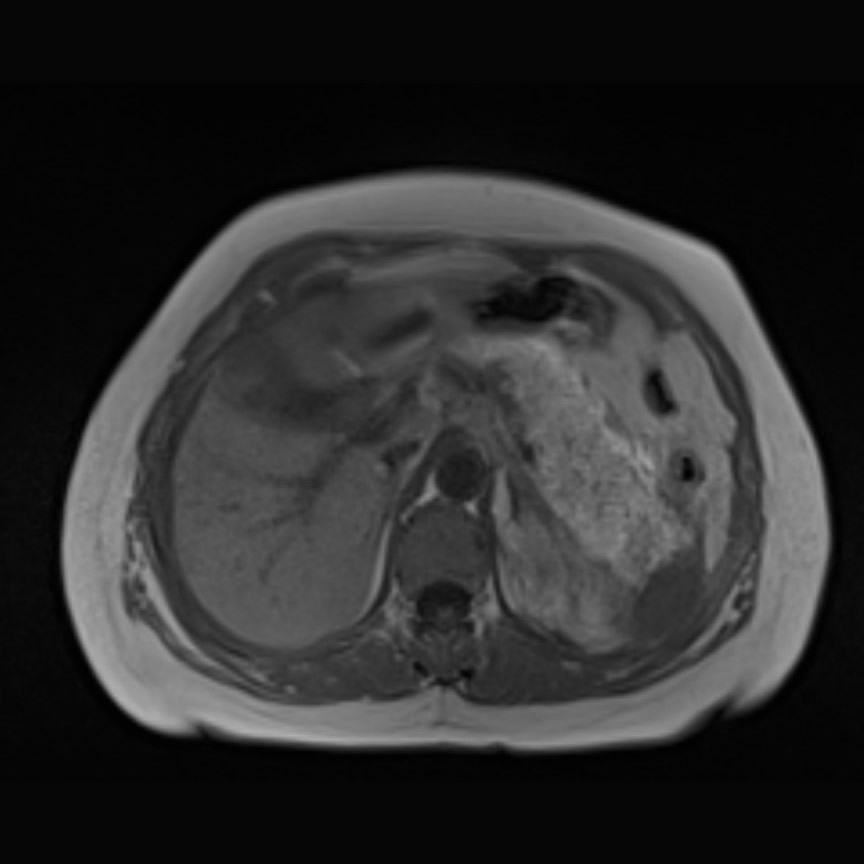

Paciente de sexo femenino de 58 años, niega antecedentes personales patológicos, consulta por dolor abdominal en hipocondrio derecho.